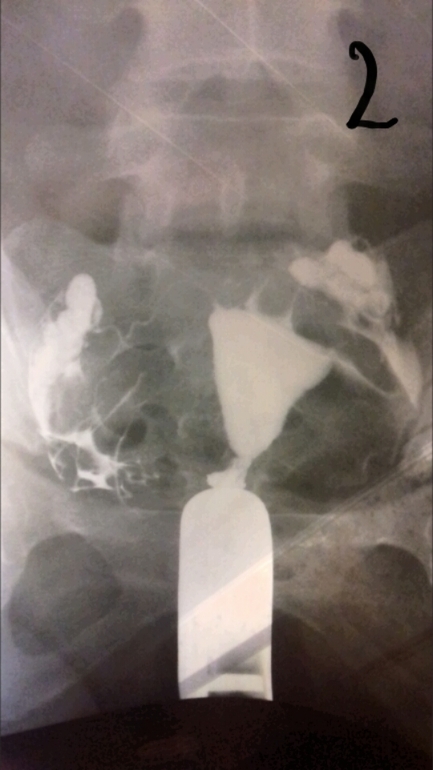

Лапароскопия, гистероскопияДобрый день девочки. Не знаю раздел куда написать, но думаю сюда. Сделала я гсг проверку труб рентгеном. Жидкость прошла, но не сразу, минут так 5 думаю лежала, хотя может меньше. Показало спайки в брюшной полости и вроде как в ампулярных отделах, так как они были расширены при поступлении контраста. И также сказали, что спайки скорее всего из-за эндометртоза. Кто сталкивался с такими проблемами, может подскажите, что по этому и по снимкам.

Полностью согласна. Все эти процедуры ведут только к лапаре. И гистероскопия также проводится в диагностических целях. Ну пробьют они раствором трубы, но это я думаю особой пользы не приносит. На снимках видно, что жидкость изливается в брюшную полость, значит проходимость есть, но если частичная, это уже не то. Так что не тчните, ларара, пару месяцев если еб нет и на Эко.